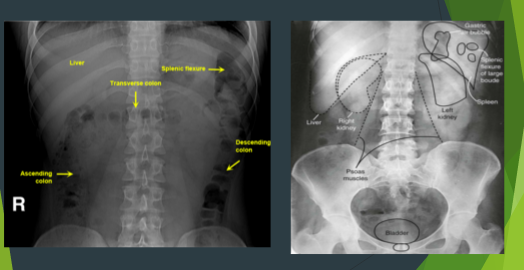

What is the soft tissue in the LUQ, size of a fist?

spleen

Can be seen, obscured, or not at all

Kidney shape?

Which is higher than the other?

What size?

Bean shaped

Left higher than right

About 3 vertebrae in size

Explain where you will find the psoas muscles on the xray?

Forms straight lines extending inferolaterally from lumbar spine to lesser trochanter of femur

Bladder appears how on the xray?

If full appears as soft tissue density in pelvis

Normal Gas Pattern

See picture

Abdominal organs